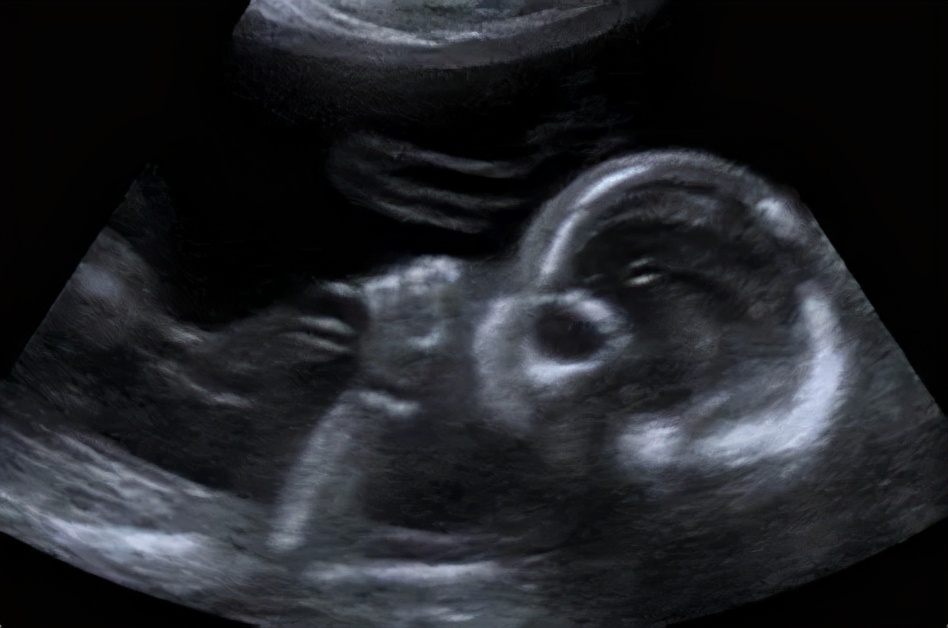

甚至有超声显示,孩子在娘胎里,就已经开始吃手了!

图源:babycenter